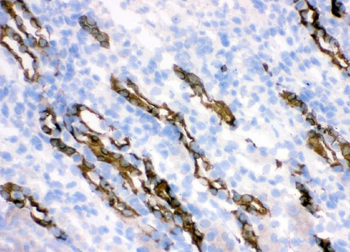

100 μg, 10 μg - Anti-CPI17 alpha/PPP1R14A Antibody [orb19175]

FC, ICC, IF, IHC, WB

Human, Mouse, Rat

Rabbit

Polyclonal

Unconjugated

10 μg, 100 μg